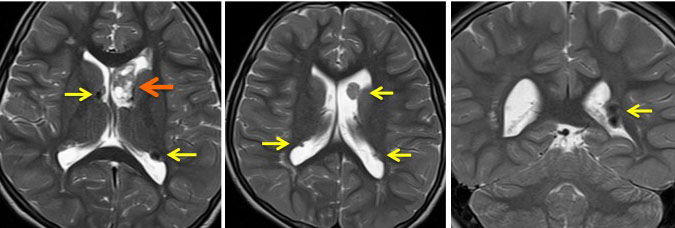

結節性硬化症 TSに見られる多発性上衣下結節 subependymal nodules

32歳で初めて睡眠時てんかん発症した患者さんのものです。側脳室壁だけに無数の上衣下結節がありますが,治療の必要はありません。SEGAではありません。

黄色の矢印で示すように脳室の壁に多数の小結節 (subependymal nodule SEN) があります。これらの結節はCTでは石灰化としてはっきり描出されますからCTの方が見やすいといえます。赤の矢印で示したのは,左前角 (caudothalamic groove) の腫瘍はSEGAですが,8年間観察してもほとんど増大しませんでした。でも今後に大きくなる可能性は否定できないものですから,これから何年も経過観察が必要です。

黄色の矢印は右の三角部のSEGAです。右の写真で大脳の皮質下白質が白くにじんで見える大脳皮質結節(cortical tubers) のも結節性硬化症の特徴です。このような病変がてんかん発作を生じます。